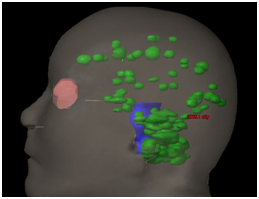

30-year-old man, with lung cancer treated with chemotherapy and complete response to his primary tumor. In extension images studies at 6months he presents multiple brain metastases without evidence of progression in another site. We propose SRS to all visible lesions: 24 (twenty-four). The total volume of disease was 15cc and the dose prescription of SRS was 27Gy in 3 fractions (Figure 3) (Figure 4). The treatment technique for this case was the same as that used for the previous patient. After 1year of follow-up, there was no neurocognitive impairment without systemic progression and in the brain resonance complete response was seen in 100% of the lesions.

Figure 3 24 metastases, dose distributions.